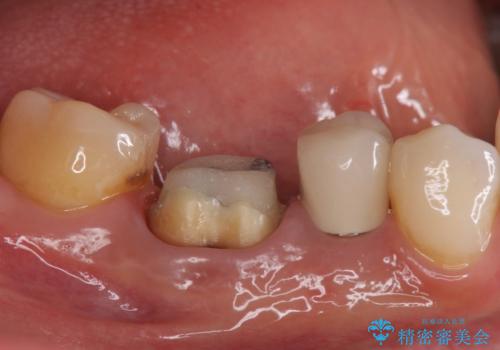

目立つ銀歯を白くしたい ジルコニアクラウンでの修復

- 口を開けたときに下の歯の銀歯が目立つから白くしたいとのことで来院されました。

根管治療はご希望されなかったため、被せ物のみをやり替えていきます。

- 右下6 仮歯+ジルコニアクラウン 11,000円+121,000円費用は治療当時の料金となります